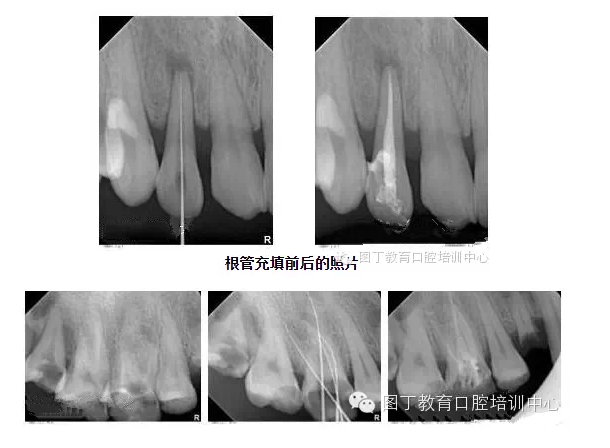

根管充填

總結(jié)幾個要點:

1,根管充填到位的前提是根管要預備好;

2,把握好充填長度;

3,選擇合適的主膠尖意義很大——合適的主尖其尖端恰好封閉根尖孔;

4,糊劑適量即可,因為充填的主體是牙膠。

5,側(cè)方加壓后的垂直加壓不可忽視,因為通過垂直加壓后的充填體更嚴實。